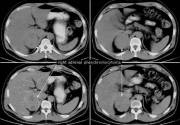

| 08:25, 9 בנובמבר 2012 | שאתותכבד810a.png (קובץ) |  |

278 קילו־בייטים | Motyk | 2 | |